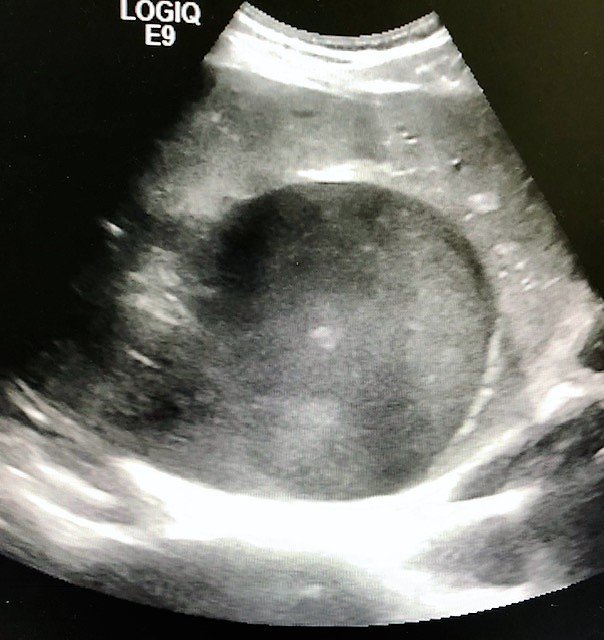

Although rare in the developed world, amebic infections are common worldwide and represent a challenging and often overlooked diagnosis. In this case, an amebic liver abscess was discovered in a 29-year-old male who presented to the emergency department (ED) complaining of right upper quadrant abdominal pain, weight loss, non-bilious/non-bloody vomiting, and diarrhea for three months. He recently traveled to India and Mexico. Point-of-care ultrasound discovered a liver mass and computed tomography (CT) confirmed the presence of a liver abscess. The case highlights the usefulness of ultrasound as an initial diagnostic tool, the importance of careful travel history in patients with suspected infectious diseases, and the initial provision of broad-spectrum coverage for bacterial and amebic pathogens for liver abscesses until the pathogen has been identified.